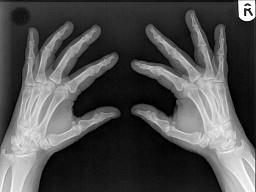

男,根据其正常手的影像图像,判断其最可能的年龄?(?)A.16岁左右B.26岁左右C.36岁左右D.76岁左右E.56岁左右

问题 男,根据其正常手的影像图像,判断其最可能的年龄?(?)

选项 A.16岁左右 B.26岁左右 C.36岁左右 D.76岁左右 E.56岁左右

答案 E